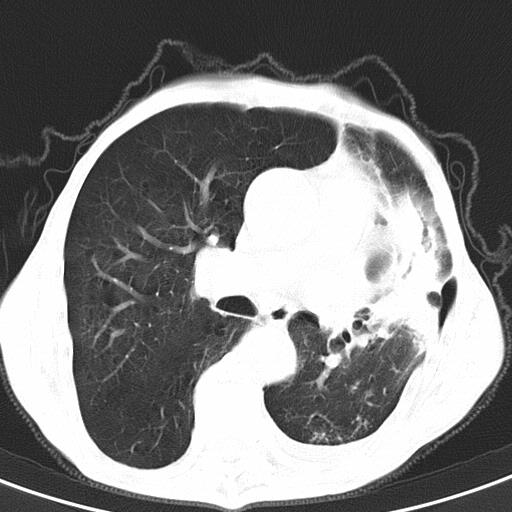

患者78岁,咳嗽胸闷一年余,近月来左侧胸痛;

患者左侧胸廓塌陷说明是长期病变,考虑tb性胸膜炎可能性大,另外有明显的肺气肿,建议行结核菌素实验,或者增强扫描

1.慢支肺气肿。2.左肺感染,建议治疗后复查。3.左侧少量胸水。

1.慢支肺气肿。2.左肺感染,建议治疗后复查,待除外继发性肺结核合并感染。3.左侧少量胸水。

1)考虑左肺慢性感染性病变(结核可能)。2)左肺上叶周围型肺癌不排除;建议追踪复查。3)肺气肿。4)左侧胸腔积液,左侧胸膜增厚、粘连。

1)考虑左肺慢性感染性病变(结核可能)。2)肺气肿。4)左侧胸腔积液,左侧胸膜增厚、粘连。3)左肺上叶周围型肺癌不排除;建议追踪复查。